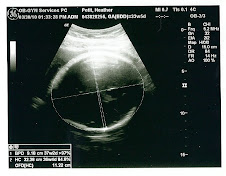

Sorry I have not posted in so long. There are a few updates since the last post of course. As of 3 weeks ago, Sydney was approximately 5 lbs. 5 oz. but her head was in the 95 percentile! YIKES! The doctor said it is just genetics and she will be a smart one. But that head of hers still has to come out! The gestational diabetes (GD) has been okay and my sugar has been great so they haven't had to increase the medication at all. I had a beautiful shower on March 20th with all of my friends and family. Thanks to Mama , Rachel, Bone, Dad and my aunts for all they did to make it so special! Sydney's nursery is now painted and just needs to have the wall decorations put on and her stuff unpacked. They gave us an inducement date of May 6th at 8:00 a.m. if she doesn't come by then, but the doc said she could come anytime. Next week I will post another update because they are going to check for dilation on Monday and do another growth ultrasound on Tuesday to see how big she is. Make sure to check out the new pics from the last ultrasound. Keep us in your prayers!